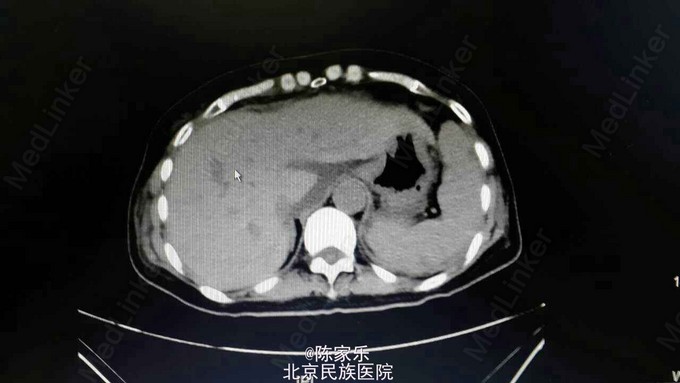

主诉:上腹部疼痛伴呕血2小时 现病史:女,55岁,2小时前无明显诱因突发上腹部疼痛,疼痛无向他处放射,伴恶心、呕暗红色血,量血100ml,无腹胀、腹泻、头晕、心季等不适。 既往史:1个月前因胰头癌行胰十二指肠切除术。否认高血压、糖尿病、肝炎、胃溃疡病史。

查体:腹部平软,上腹部轻压痛,无肌紧张、反跳痛。 实验室检查:未见明显异常 CT:胰十二指肠切除术后改变,肝门区及肝周积液,肝右叶近包膜区低密度灶,肝内胆管轻度扩张。